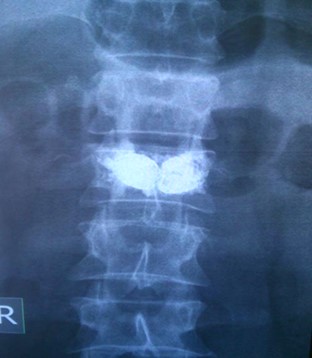

Multisegmentna Vertbroplastika

View the embedded image gallery online at:

https://www.klinikaelit.com/minimalno-invazivne-porcedure#sigProId42e6fa39e8